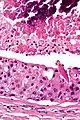

Intermed. mag.